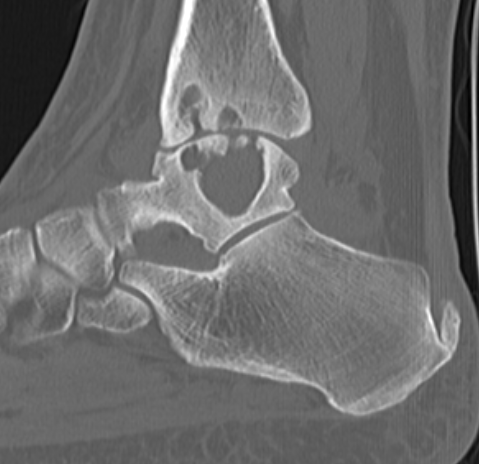

Synovial osteochondromatosis

Chondroid metaplasia of synovium (synovial chondromatosis)

- form nodules of hyaline cartilage

- break free into joint

- lesions can mineralize or ossify (Synovial osteochondromatosis)

Ankle